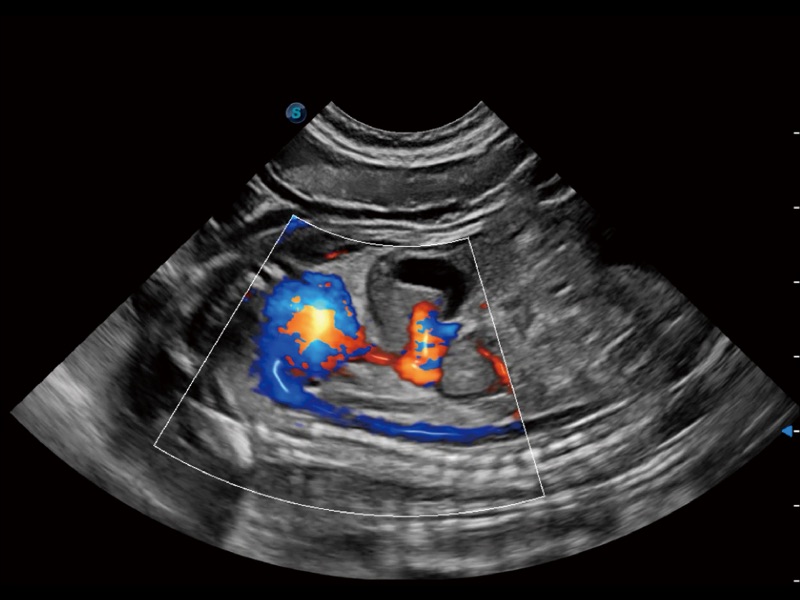

(犬)四腔心

(犬)胎儿主动脉弓立体血流

优异的基础图像

ProPet 70 全新的动物超声智能软件和丰富的探头群,为动物医生提供了高清晰度和精细分辨率的图像,无论在宠物、马科、畜牧还是实验室动物等应用中都可以轻松应对,为您的日常工作带来满意的体验。